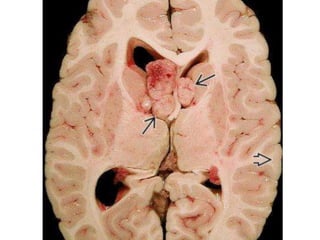

Cortical Tubers • Corticaltubers are firm, whitish, pyramid-shaped, elevated areas of smooth gyral thickening, with or without central depressions, that grossly resemble potatoes ("tubers") • On CT scan, Seen as hypodense cortical/subcortical masses within broadened and expanded gyri Calcifications in cortical tubers increase with age • Tubers in older children and adults demonstrate mixed signal intensity on T2/FLAIR

• #27 Axial cut section from the same case shows bilateral subependymal giant cell astrocytomas

• Cortical Tubers –Broad, expanded gyrus – CT: Initially hypodense; Ca++ ↑ with age • 50% of patients eventually develop ≥ 1 calcified tuber(s) – MR: Periphery isointense, subcortical portion T2/FLAIR hyperintense • Subependymal Nodules – CT: Ca++ rare in first year; ↑ with age • 50% eventually calcify • Don't enhance – MR: T1 hyper-, T2 hypointense; 50% enhance • White Matter Lesions – T2/FLAIR hyperintense radial lines/wedges • Subependymal Giant Cell Astrocytoma – CT: Mixed-density mass at foramen of Monro, moderate enhancement – MR: Heterogeneous signal, strong enhancement